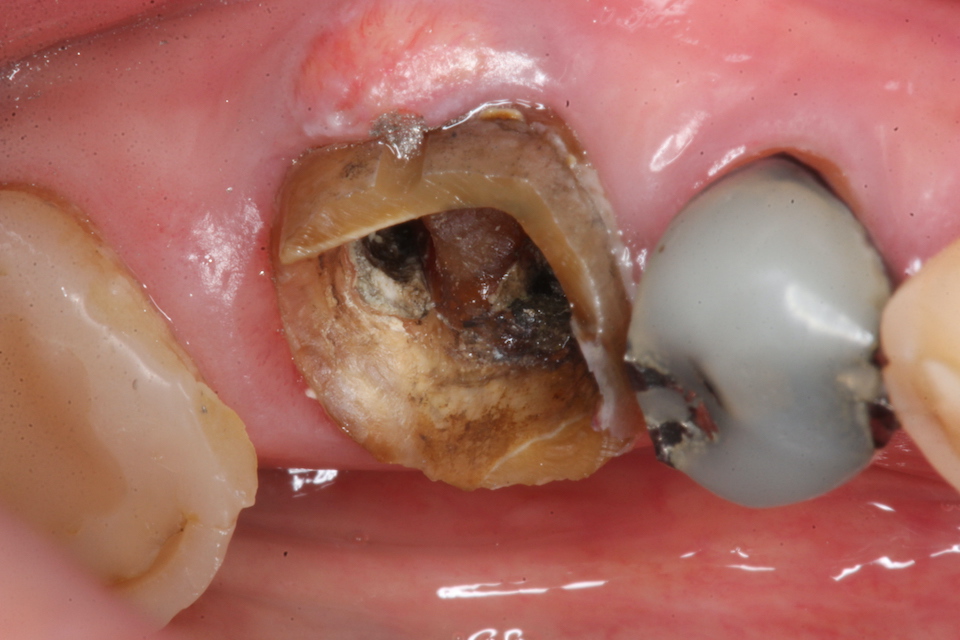

今日の抜歯再植術シリーズ39.1 2025.11.14